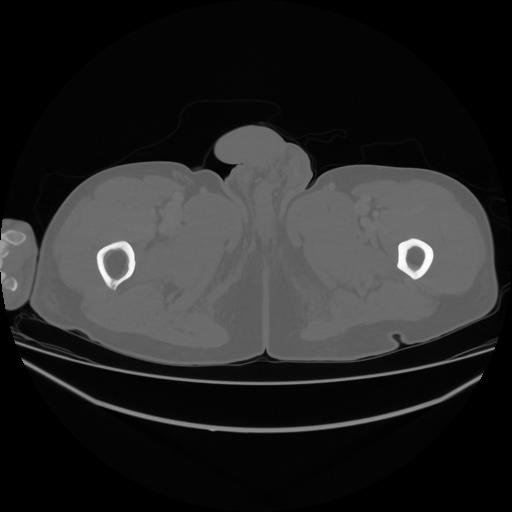

5 CUERPO,CE,Vol,1.0,CUERPO,,